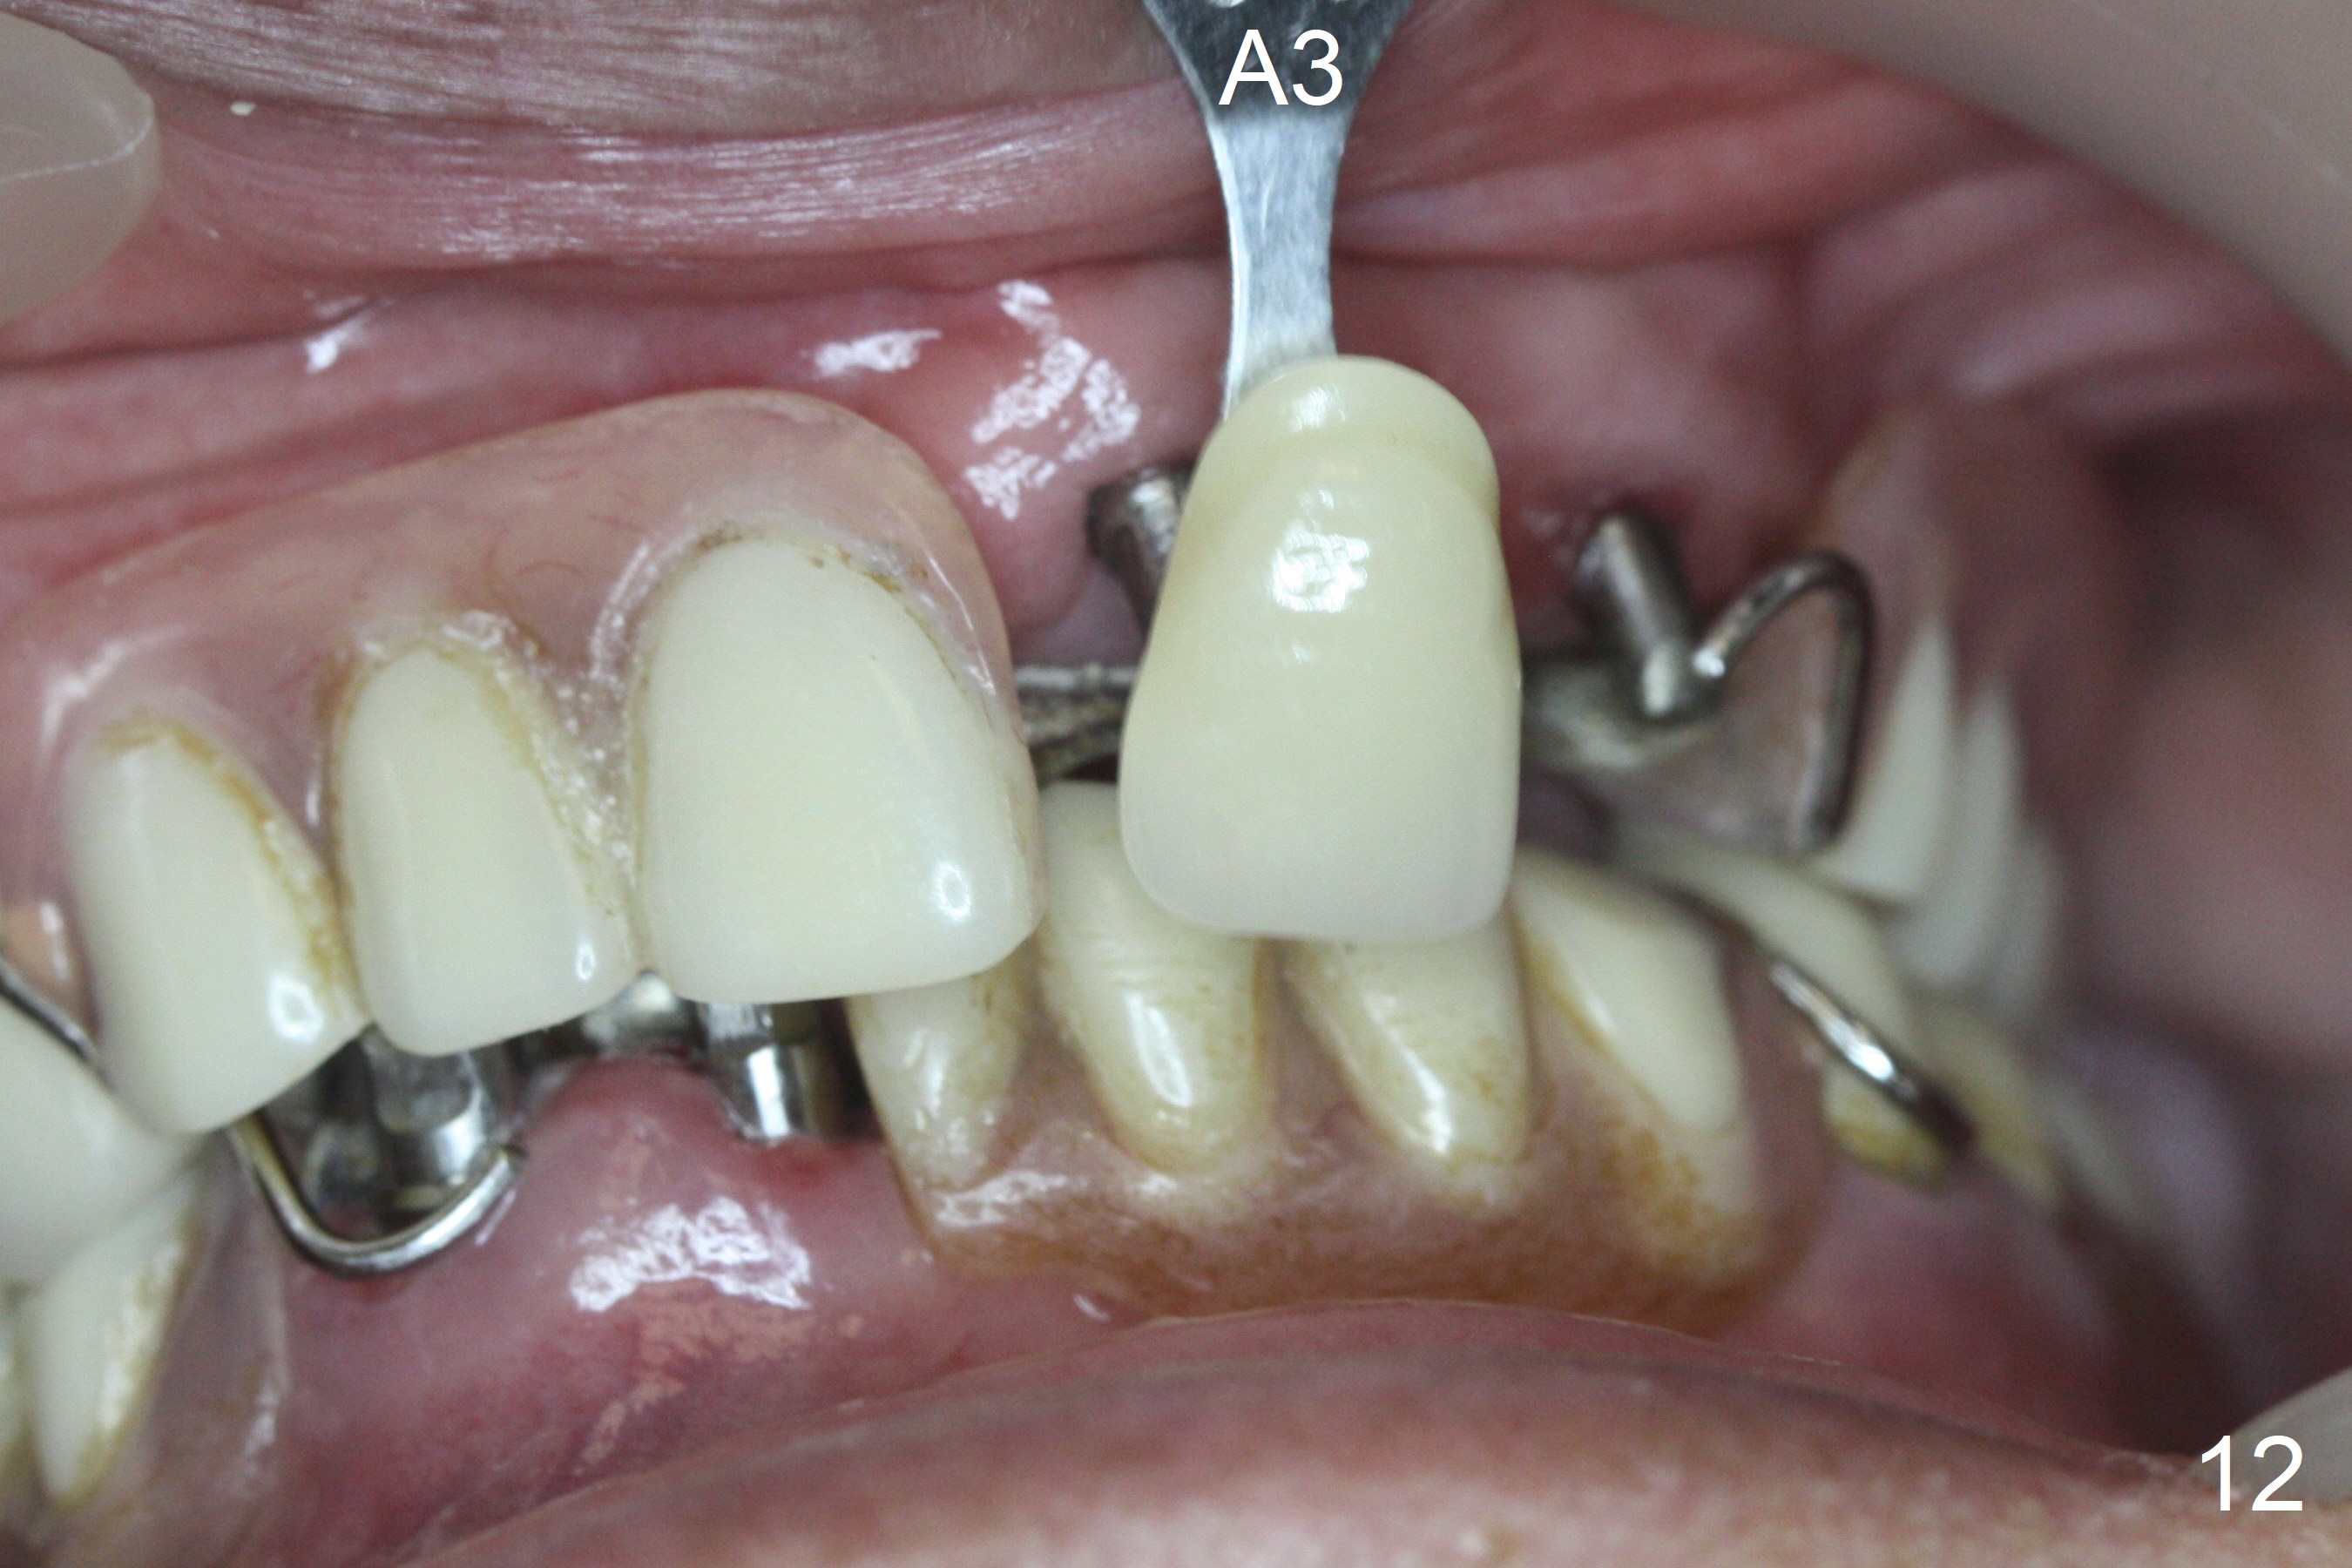

Incision reveals that the ridge at #9 and 11 is narrower than expected. A 3x14 mm 15º 1 piece implant is placed at the site of #9, while a 3x17 mm straight 1-piece one is placed at #11 (Fig.1,4). Insertion torques at #9 and 11 are 20 and 30 Ncm, respectively. The relatively low insertion torque is partially due to osteoporosis. The 65-year-old lady also has dry mouth. Osteotomy should be underprep. The position and trajectory of the implants are dictated by the partial denture (Fig.2). After minor abutment adjustment (Fig.3), an immediate provisional bridge is fabricated. There is no interference when the partial is removed and inserted. After bone graft (Fig.4 ^) and Osteogen Membrane, the ridge (Fig.3) is wider than before. The patient returns for reline 2 months postop (Fig.5-7). In spite of insufficient oral hygiene, the gingiva remains healthy around the implants. To form distinct papillae, acrylic should be added to (Fig.8 yellow line) and removed from (hushed area) the individual provisional crowns. One month after provisional modification (Fig.10, as compared to Fig.5), the pontic recipient site is concave (Fig.11) and becomes less concave after cord packing and abutment trimming. When the provisional bridge is reseated after impression (Fig.12), the pontic recipient site must be blanched again. Please trim the pontic recipient site of the model ~ .5 mm to enhance cosmetics. Water Pik has been used since surgery, but it may be related to loss of bone graft 3.5 months postop (Fig.9 *). One month post cementation, the patient has complained of pain when water pik is irrigating the gingiva palatal to the FPD, apparently in association with denture-related Candidiasis. Two weeks of use of Mycostatin Oral Suspension, peri-implantitis or peri-implant mucositis-like signs and symptoms disappear (Fig.13). CBCT taken 6 months postop confirms that the implants appear to be have been placed in the bone (14,15). The FPD appears to be loose 2.5 years post cementation.